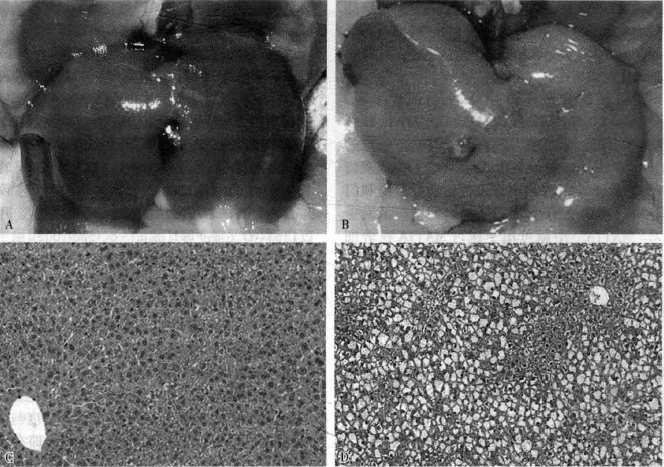

7-2 ob/ob小鼠肝臟大體及組織學圖片

注:A. ob/ob小鼠肝臟(3個月);B. ob/ob小鼠自發(fā)脂肪肝(3個月);C. H&E染色顯示ob/ob小鼠正常肝臟組織; D.H&E染色顯示ob/ob小鼠肝臟有脂肪沉積

oh/ob小鼠(ob/ob mice)是由美國Jackson實驗室于1949年偶然發(fā)現的基因隱性遺傳突變小鼠,目前是國外最常用NAFLD模型。ob/ob小鼠是由于編碼食欲抑制激素leptin的ob基因發(fā)生自發(fā)性突變,無法合成瘦素,導致過度攝食、肥胖,出現高胰島素血癥、高脂血癥及明顯的高血糖癥。組織病理學改變?yōu)楦渭毎咀冃缘龋▓D7-2/文末彩圖7-2)。普通飼料飼喂僅發(fā)生單純性脂肪肝,不會演變?yōu)榉蔷凭灾拘愿窝?nonalcoholic steatohepatitis,NASH),除非給予蛋氨酸和膽堿缺乏飲食或高脂飲食或并存其他肝損傷因素。